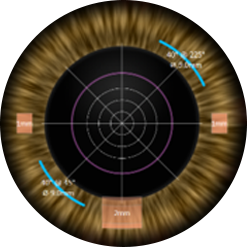

올레이저 노안백내장

균일하고 정교한

레이저 파쇄

vs